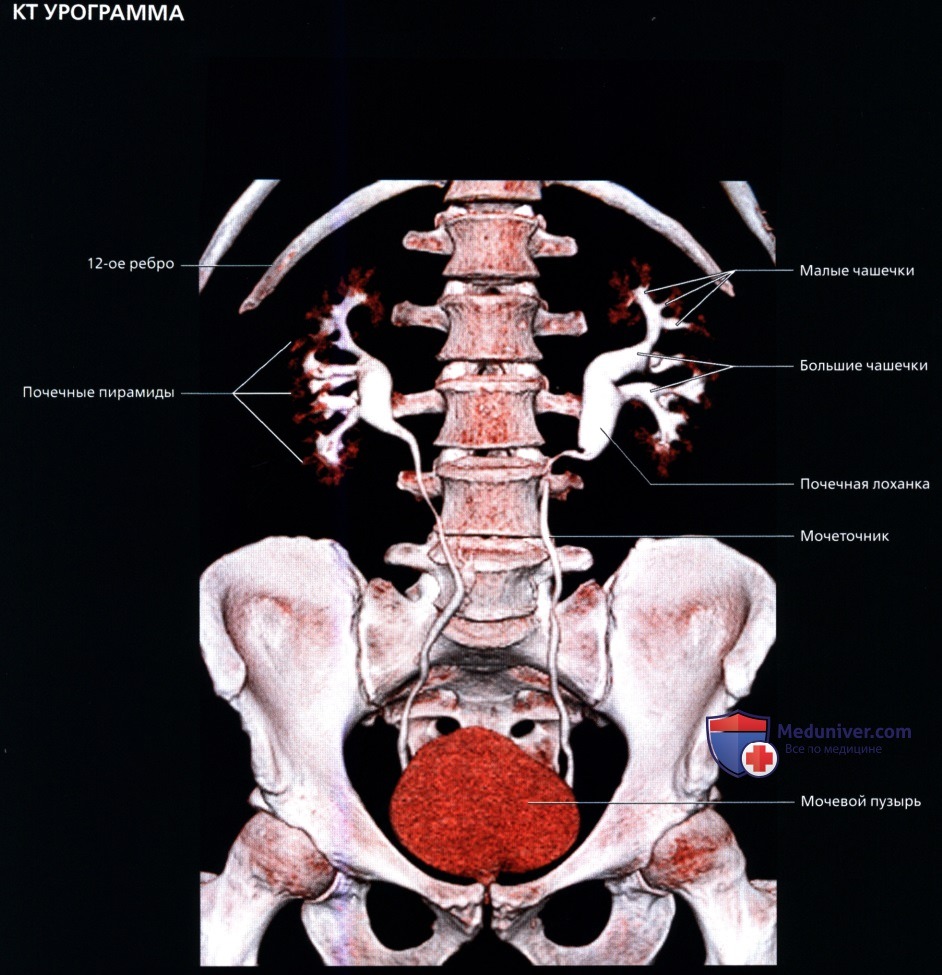

Сначала исследуют почки в продольном направлении (поясничная область), затем изучают поперечные и косые срезы, перемещая датчик на переднюю и боковые поверхности живота. При этом пациента просят поочередно повернуться на правый и левый бок. Такая техника позволяет определить локализацию (месторасположение) почек, их размеры и форму, оценить состояние паренхимы, почечных синусов, чашечек и лоханок.

Для определения подвижности почек и улучшения визуализации органов при каждом изменении положения тела врач просит больного вдохнуть и на несколько секунд задержать дыхание. На вдохе почки опускаются из-под реберной дуги и просматриваются намного лучше. УЗИ почек стоя делают при подозрении на нефроптоз (опущение одной или обеих почек).

Расшифровка результатов

Интерпретация результатов исследования выполняется только врачом-сонологом. В заключении специалист указывает количество почек, их анатомическое положение, подвижность, размер и форму, количество и состояние мочеточников, описывает структуру чашечно-лоханочного аппарата и паренхимы почек.

а) Анатомия почек:

• Почечная лоханка: расширение верхнего конца мочеточника в виде воронки:

о Собирает мочу от больших чашечек (2 или 3), каждая из которых в свою очередь собирает мочу от малых чашечек (2-4)

• Почечный сосочек: точечная верхушка почечной пирамиды, содержащей собирательные трубочки, выделяющие мочу

о Каждый сосочек открывается в малую чашечку